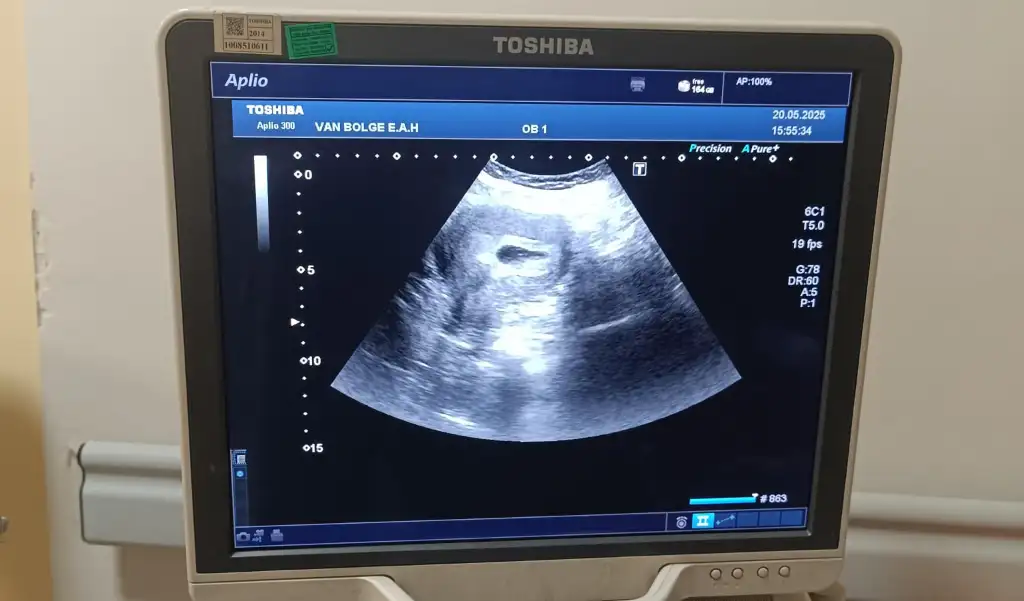

6 haftalık ve 8 haftalik yorumunuzu banada yapabilir misiniz

Eklentiler

• 1000062852.webp

1000062852.webp

27,5 KB · Görüntüleme: 65

• 1000062187.webp

1000062187.webp

29,4 KB · Görüntüleme: 78